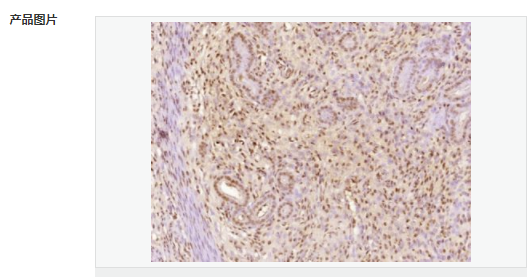

交叉反應(yīng):Human,Mouse,Rat(predicted:Dog,Pig,Cow,Horse,Rabbit,Sheep) 推薦應(yīng)用:IHC-P,IHC-F,ICC,IF

交叉反應(yīng):Human,Mouse,Rat(predicted:Dog,Pig,Cow,Horse,Rabbit,Sheep) 推薦應(yīng)用:IHC-P,IHC-F,ICC,IF

| 產(chǎn)品應(yīng)用 | IHC-P=1:100-500 IHC-F=1:100-500 ICC=1:100-500 IF=1:100-500 (石蠟切片需做抗原修復(fù)) not yet tested in other applications. optimal dilutions/concentrations should be determined by the end user. |

| 細(xì)胞定位 | 細(xì)胞核 細(xì)胞漿 |